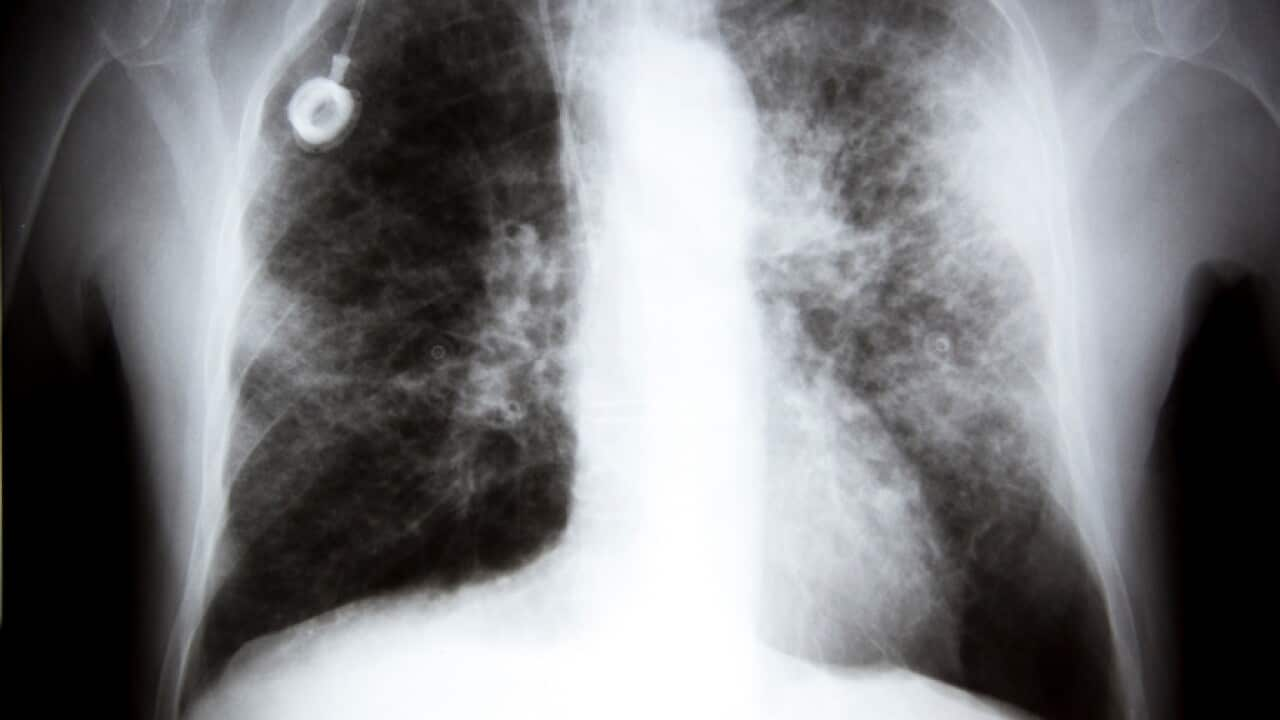

An X-ray showing lung cancer Source: Getty

Lung cancer kills 9,000 Australians each year, or 25 people a day, which is 60 per cent more than the fatality rate of bowel cancer, which is the second deadliest.